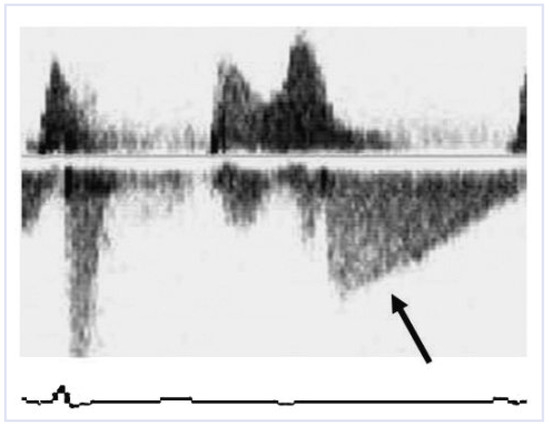

Diastolic Mitral Regurgitation

by Raban Jeger and Hans Peter Brunner-La Rocca

Abstract

A 90-year-old female patient was admitted with congestive heart failure [...] Full article

Show Figures

Figure 1